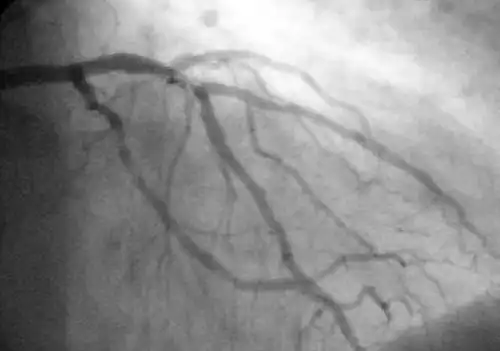

Koronarangiographie und Ventrikulographie

Mit Hilfe der diagnostischen Koronarangiographie können Koronararterien dargestellt und deren Anatomie sowie das Ausmaß und die Lokalisation eventueller Stenosen beurteilt werden. Sie ist die Untersuchung mit der besten Aussagekraft. Bei dieser Untersuchung wird ein Herzkatheter über die Arteria femoralis (Oberschenkelarterie) oder seltener über die Arteria brachialis (Oberarmarterie) bis zu den Abgängen der Koronararterien aus der Aorta vorgeschoben und Kontrastmittel in die Abgänge injiziert. Mit Hilfe von Röntgenstrahlung können die Koronararterien sichtbar gemacht und beurteilt werden.[24] Der Katheter kann, unter Überbrückung der Aortenklappe, weiter in die linke Herzkammer vorgeschoben werden. Diese Untersuchung wird als Ventrikulografie bezeichnet. Sie ermöglicht zusätzlich regionale Kontraktionsstörungen sichtbar zu machen, die zum Beispiel Hinweise auf zurückliegende Herzinfarkte bieten können, sowie eine Beurteilung der linksventrikulären Pumpfunktion über Berechnung der Auswurffraktion und die Bestimmung der Dehnbarkeit der Herzmuskulatur (Compliance) durch Bestimmung des enddiastolischen Volumens.[1]

Da es sich bei der Koronarangiographie und der Ventrikuloangiografie um invasive Untersuchungsmethoden handelt, kann es neben relativ ungefährlichen Komplikationen (beispielsweise Hämatome an der Einstichstelle) in sehr seltenen Fällen zu schwerwiegenden lebensbedrohlichen Komplikationen kommen. Dazu gehören vor allem Herzinfarkte, Schlaganfall, Spaltungen (Dissektionen) der Gefäßwände, Herzrupturen, Luftembolien und Arrhythmien.[4] Die Letalität der Untersuchung liegt unter 1:100.[1]

Aufgrund der nicht völlig ausschließbaren Risiken für das Auftreten von Komplikationen, der Strahlenbelastung sowie der Belastung der Nieren durch das Röntgenkontrastmittel, sollte die Indikation der Koronarangiographie zur Diagnose einer chronischen KHK relativ streng gestellt und im Sinne einer Nutzen-Risikoanalyse abgewogen werden. Nach den Empfehlungen der nationalen Versorgungsleitlinie (NVL) sollte diese Untersuchung nur dann erfolgen, wenn entweder alle nicht-invasiven Untersuchungsmethoden ohne Ergebnis ausgeschöpft wurden und trotzdem die Verdachtsdiagnose chronische KHK wahrscheinlich ist, oder wenn der Patient von Revaskularisationsmaßnahmen profitieren könnte.[4] Bei der Abwägung spielen des Weiteren bestehende kardiovaskuläre Risikofaktoren, zurückliegende Herzinfarkte und andere bestehende Herz-Kreislauf-Erkrankungen, die Einschätzung der Lebensqualität durch den Patienten sowie der Schweregrad der stabilen Angina pectoris nach CCS-Klassifikation eine wichtige Rolle. Für Letztere gilt, dass bei einem CCS-Stadium < III sowie bei erfolgreicher konservativer Pharmakotherapie, normalerweise keine Indikation für eine erneute Koronarangiografie besteht.[4]

Als diagnostische und therapeutische Maßnahme gilt die Darstellung der Herzkranzgefäße mittels Koronarangiographie als Goldstandard in der Diagnostik. In derselben Sitzung ist es möglich, signifikante Engstellen durch eine Ballondilatation (Perkutane transluminale coronare Angioplastie, PTCA), ggf. kombiniert mit der Implantation eines Stents aufzudehnen.